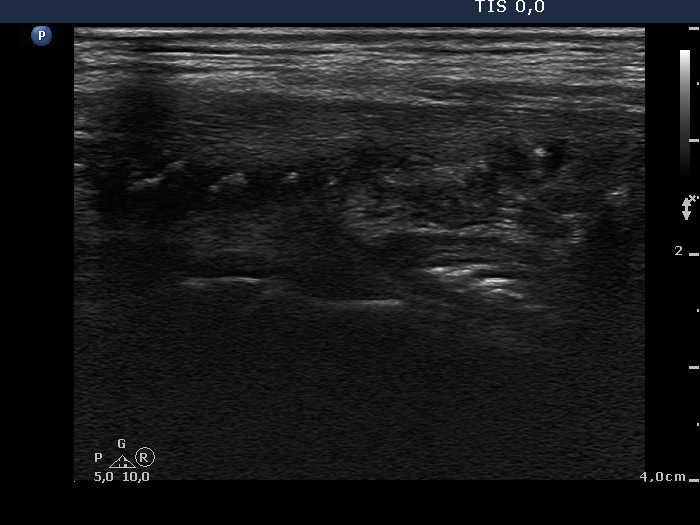

One month after surgery (second row of images):

Clinical data: The patient had no complaints.

Palpation: There was a relatively large, painless mass in the left thyroid bed.

Result of blood test: euthyroidism on daily 125 microgram levothyroxine (TSH 0.87 mIU/L).

Ultrasonography. The thyroid parenchyma was replaced by regenerative tissue. There was a cystic lesion in the left thyroid bed with a maximal diameter of 23 mm.